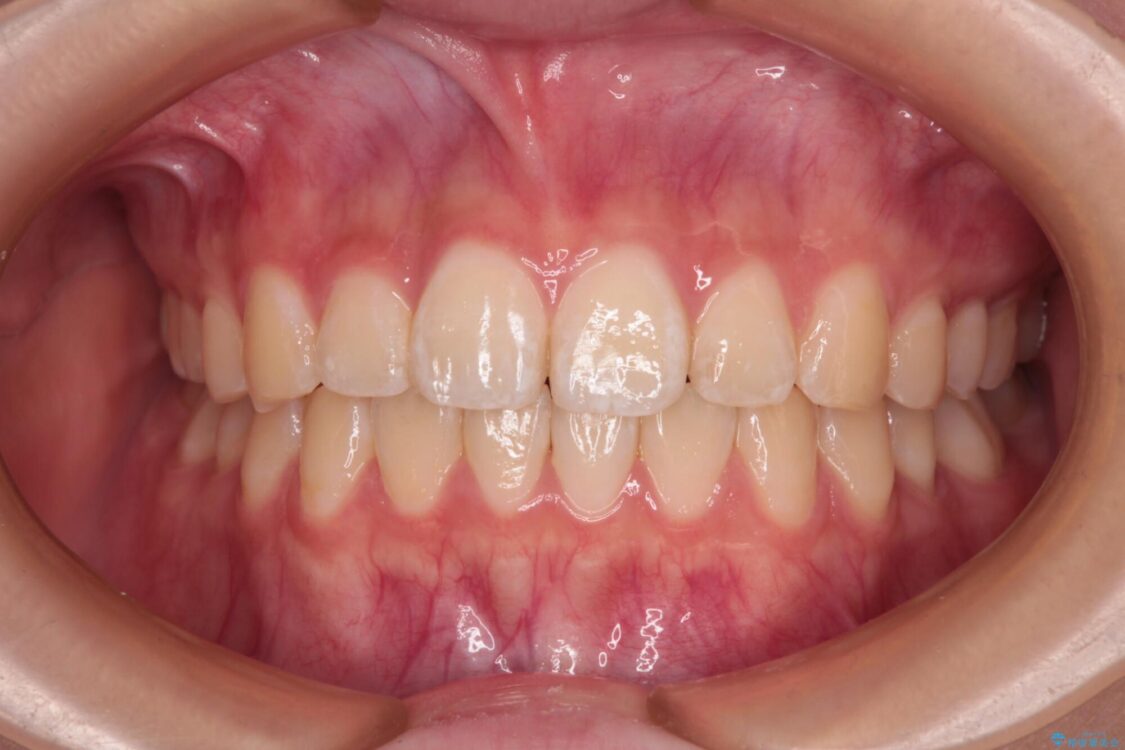

治療前

• インビザラインは使える自信がない ワイヤー装置にて矯正治療 治療前画像